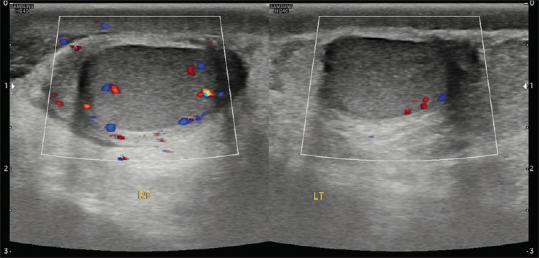

Acute Scrotal Pain - Role of Sonographic Evaluation in Solving Diagnostic Dilemma.